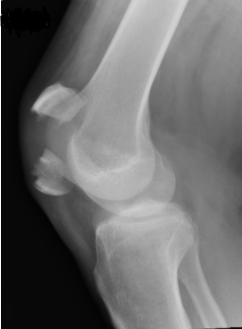

A 50 yo M with no PMHx presents to the ED with knee pain after falling from standing height. He tripped in his kitchen and fell directly on his knee. He has severe pain with any movement. There is a palpable deformity and he is unable to extend his knee on exam. He is neurovascularly intact distal to the knee. An xray is done and shown below. What's the diagnosis? (scroll down for answer)

Answer: Acute Patellar Fracture